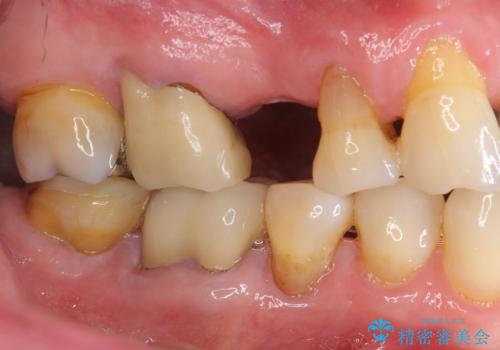

失った奥歯のインプラント治療

- 失ったままで放置していたインプラント治療を希望され来院されました。

抜歯後から十分に時間が経過しており、すぐにインプラントの埋入を計画できる状態です。

「失った1本の歯の機能回復を行うだけでもずいぶん咬めるようになった。」、と咬合機能の回復を実感していただくことができました。